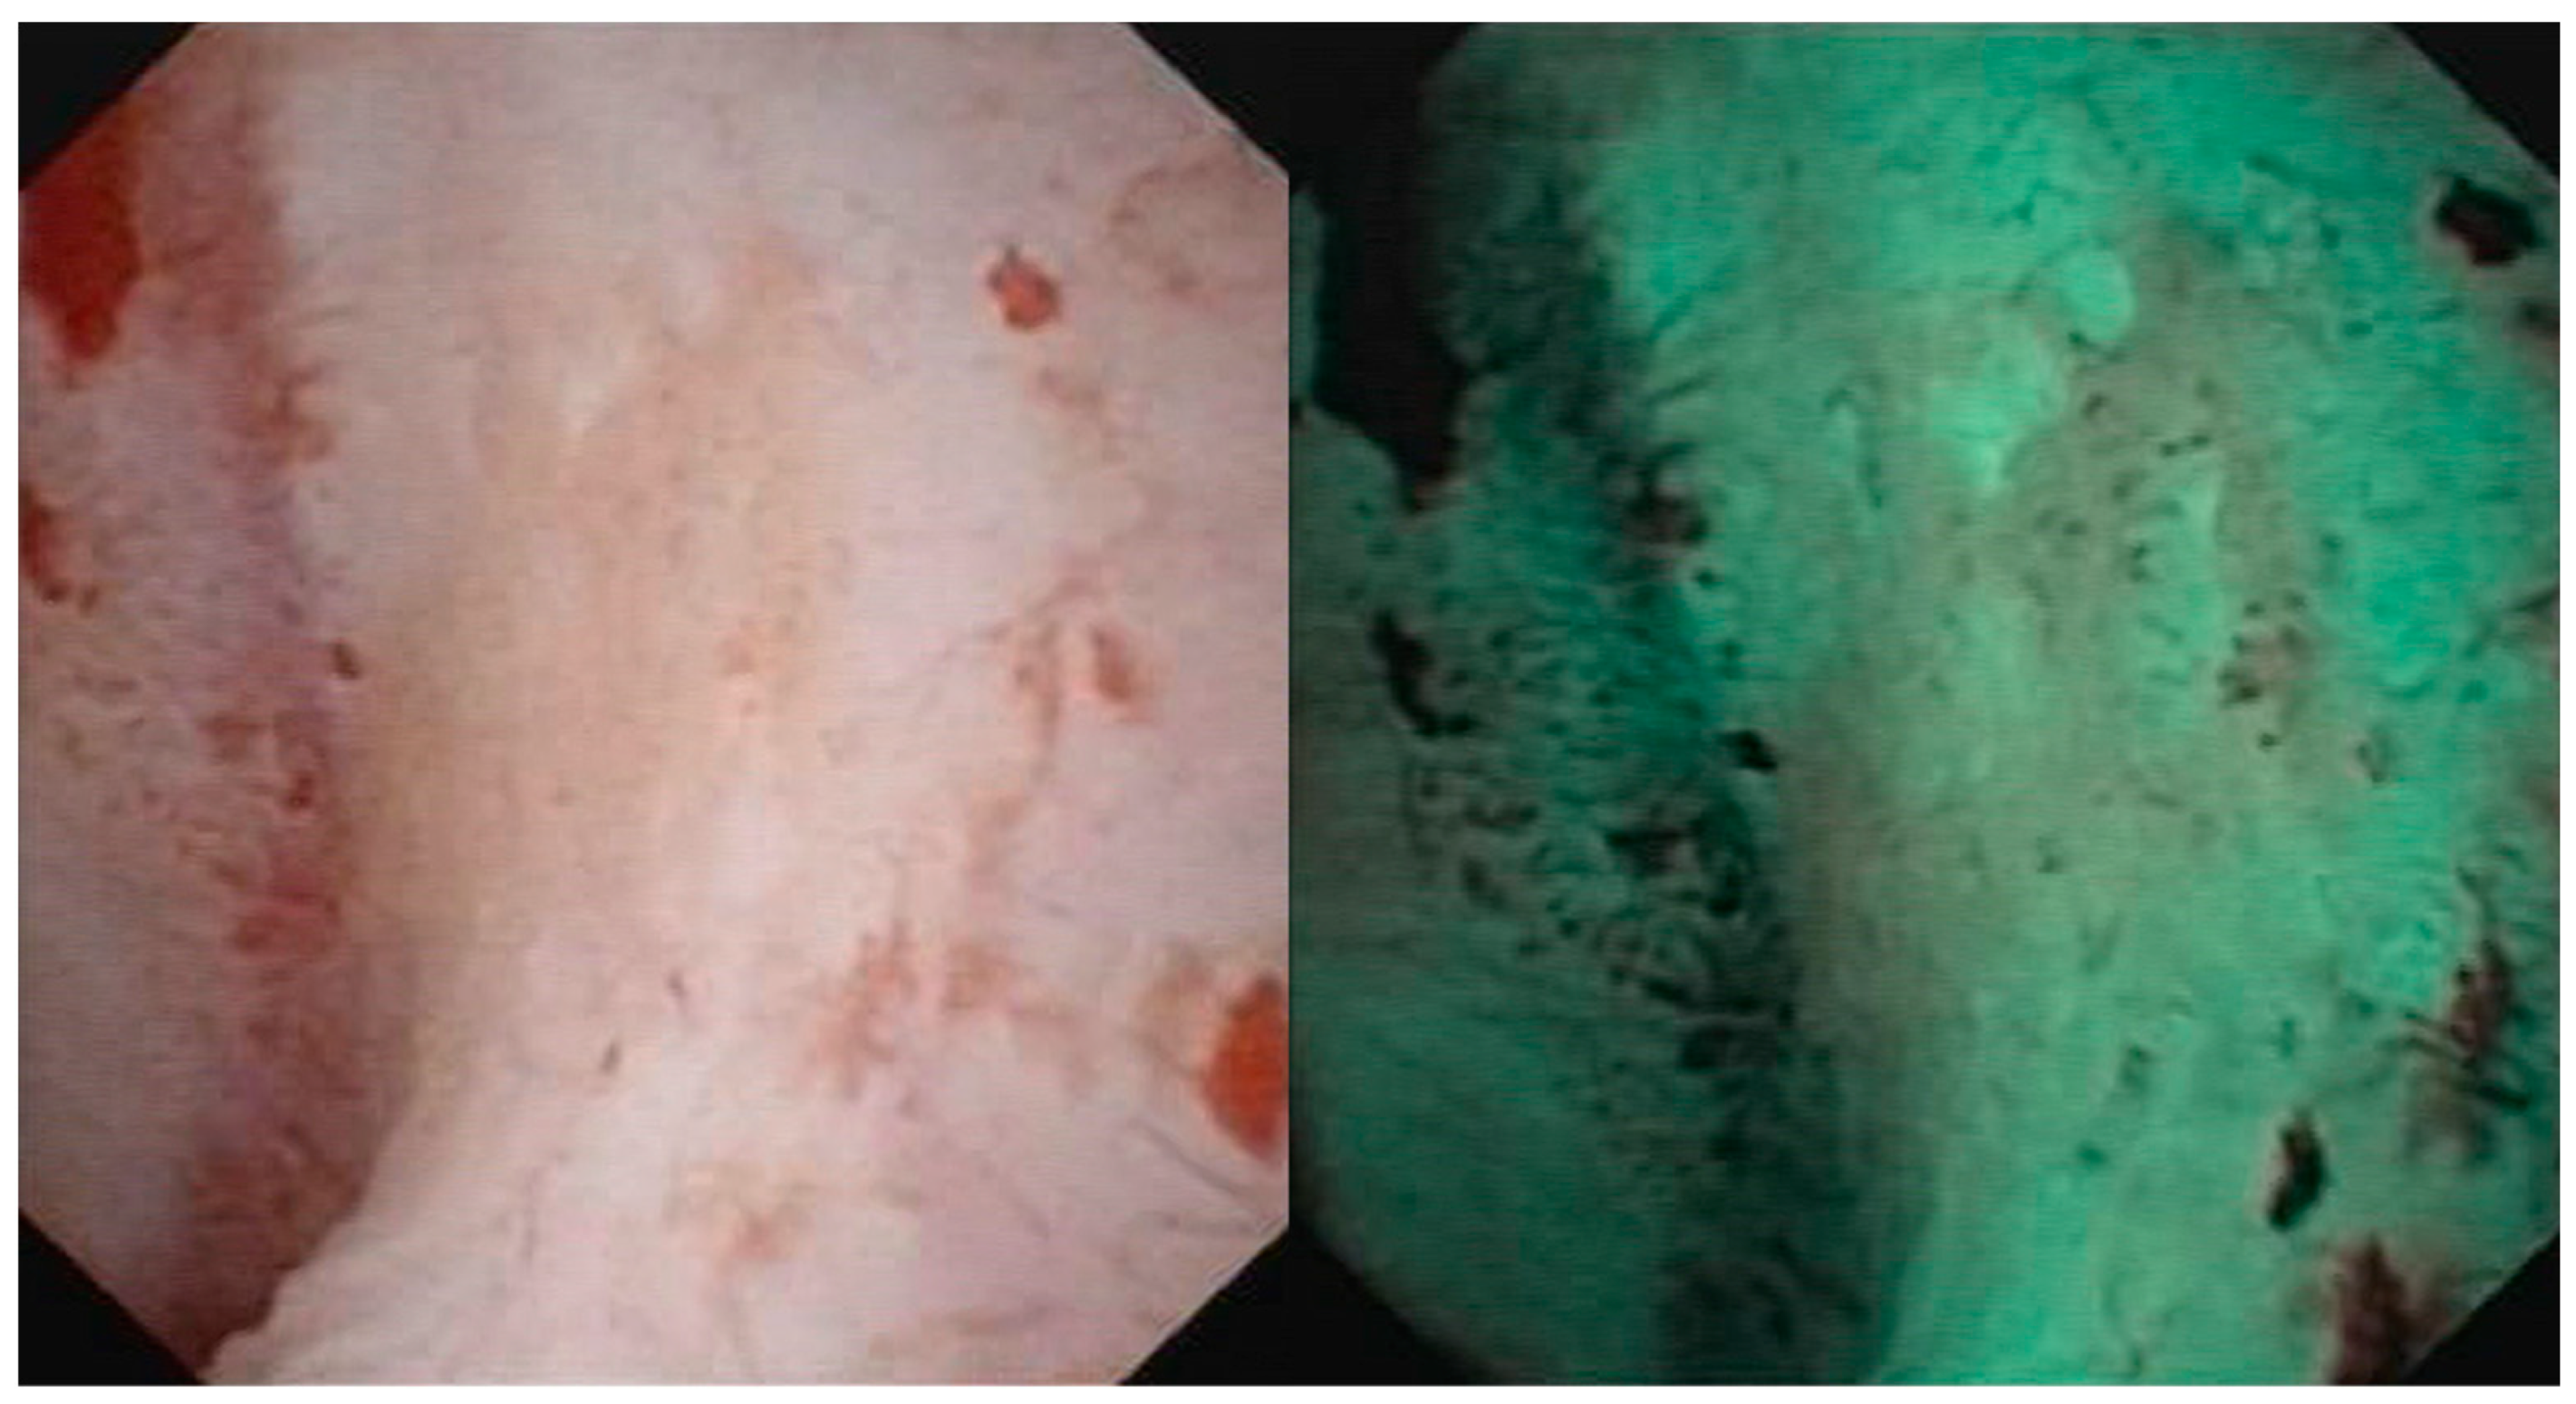

- Iordache, V.F.; Geavlete, P.A.; Georgescu, D.A.; Ene, C.V.; Păunescu, M.A.; Niculae, A.; Peride, I.; Neagu, T.P.; Bulai, C.A.; Bălan, G.X.; et al. NBI-assisted digital flexible ureteroscopy in transitional renal cell carcinoma—An evidence-based assessment “through the looking glass” of the pathological analysis. Rom. J. Morphol. Embryol. 2018, 59, 1091–1096. [Google Scholar] [PubMed]

- Meyer, F.; Al Qahtani, S.; Gil-Diez de Medina, S.; Geavlete, B.; Thomas, A.; Traxer, O. Narrow band imaging: Description of the technique and initial experience with upper urinary tract carcinomas. Prog. Urol. 2011, 21, 527–533. [Google Scholar] [CrossRef]